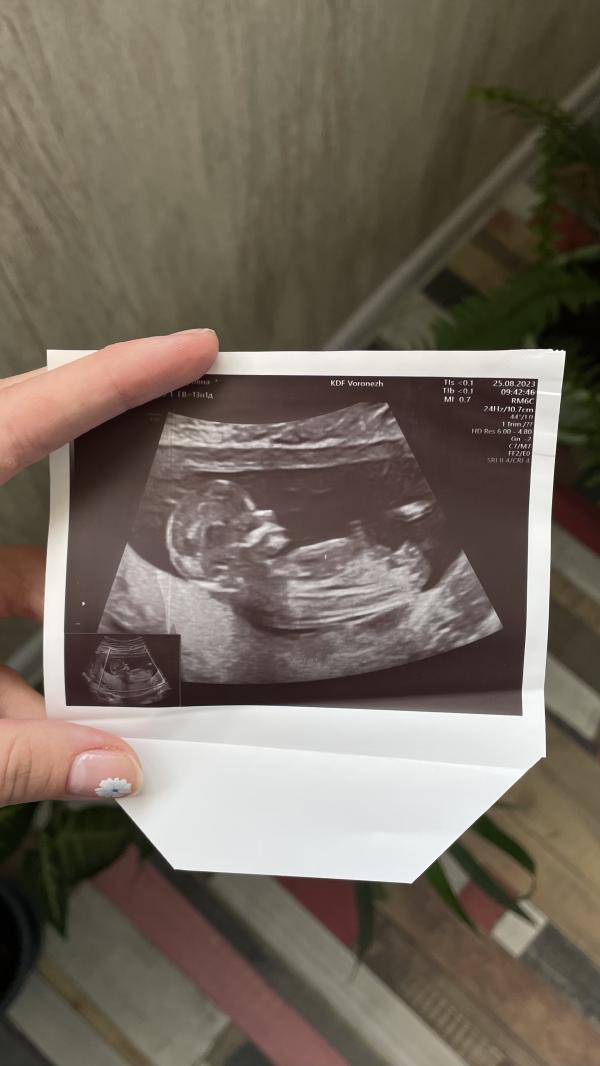

Сегодня утром ездила на первый скрининг, показали мне мою малышку 🥰

Предположила пол - девочка 🤭🎀

Малышка все время крутилась и вертелась, дрыгала ножками, толкалась ( слава богу, пока не ощущаю толчков 🤣) под конец уже улеглась)

По УЗИ все хорошо, малышка носатая 😅будем ждать результаты по крови)